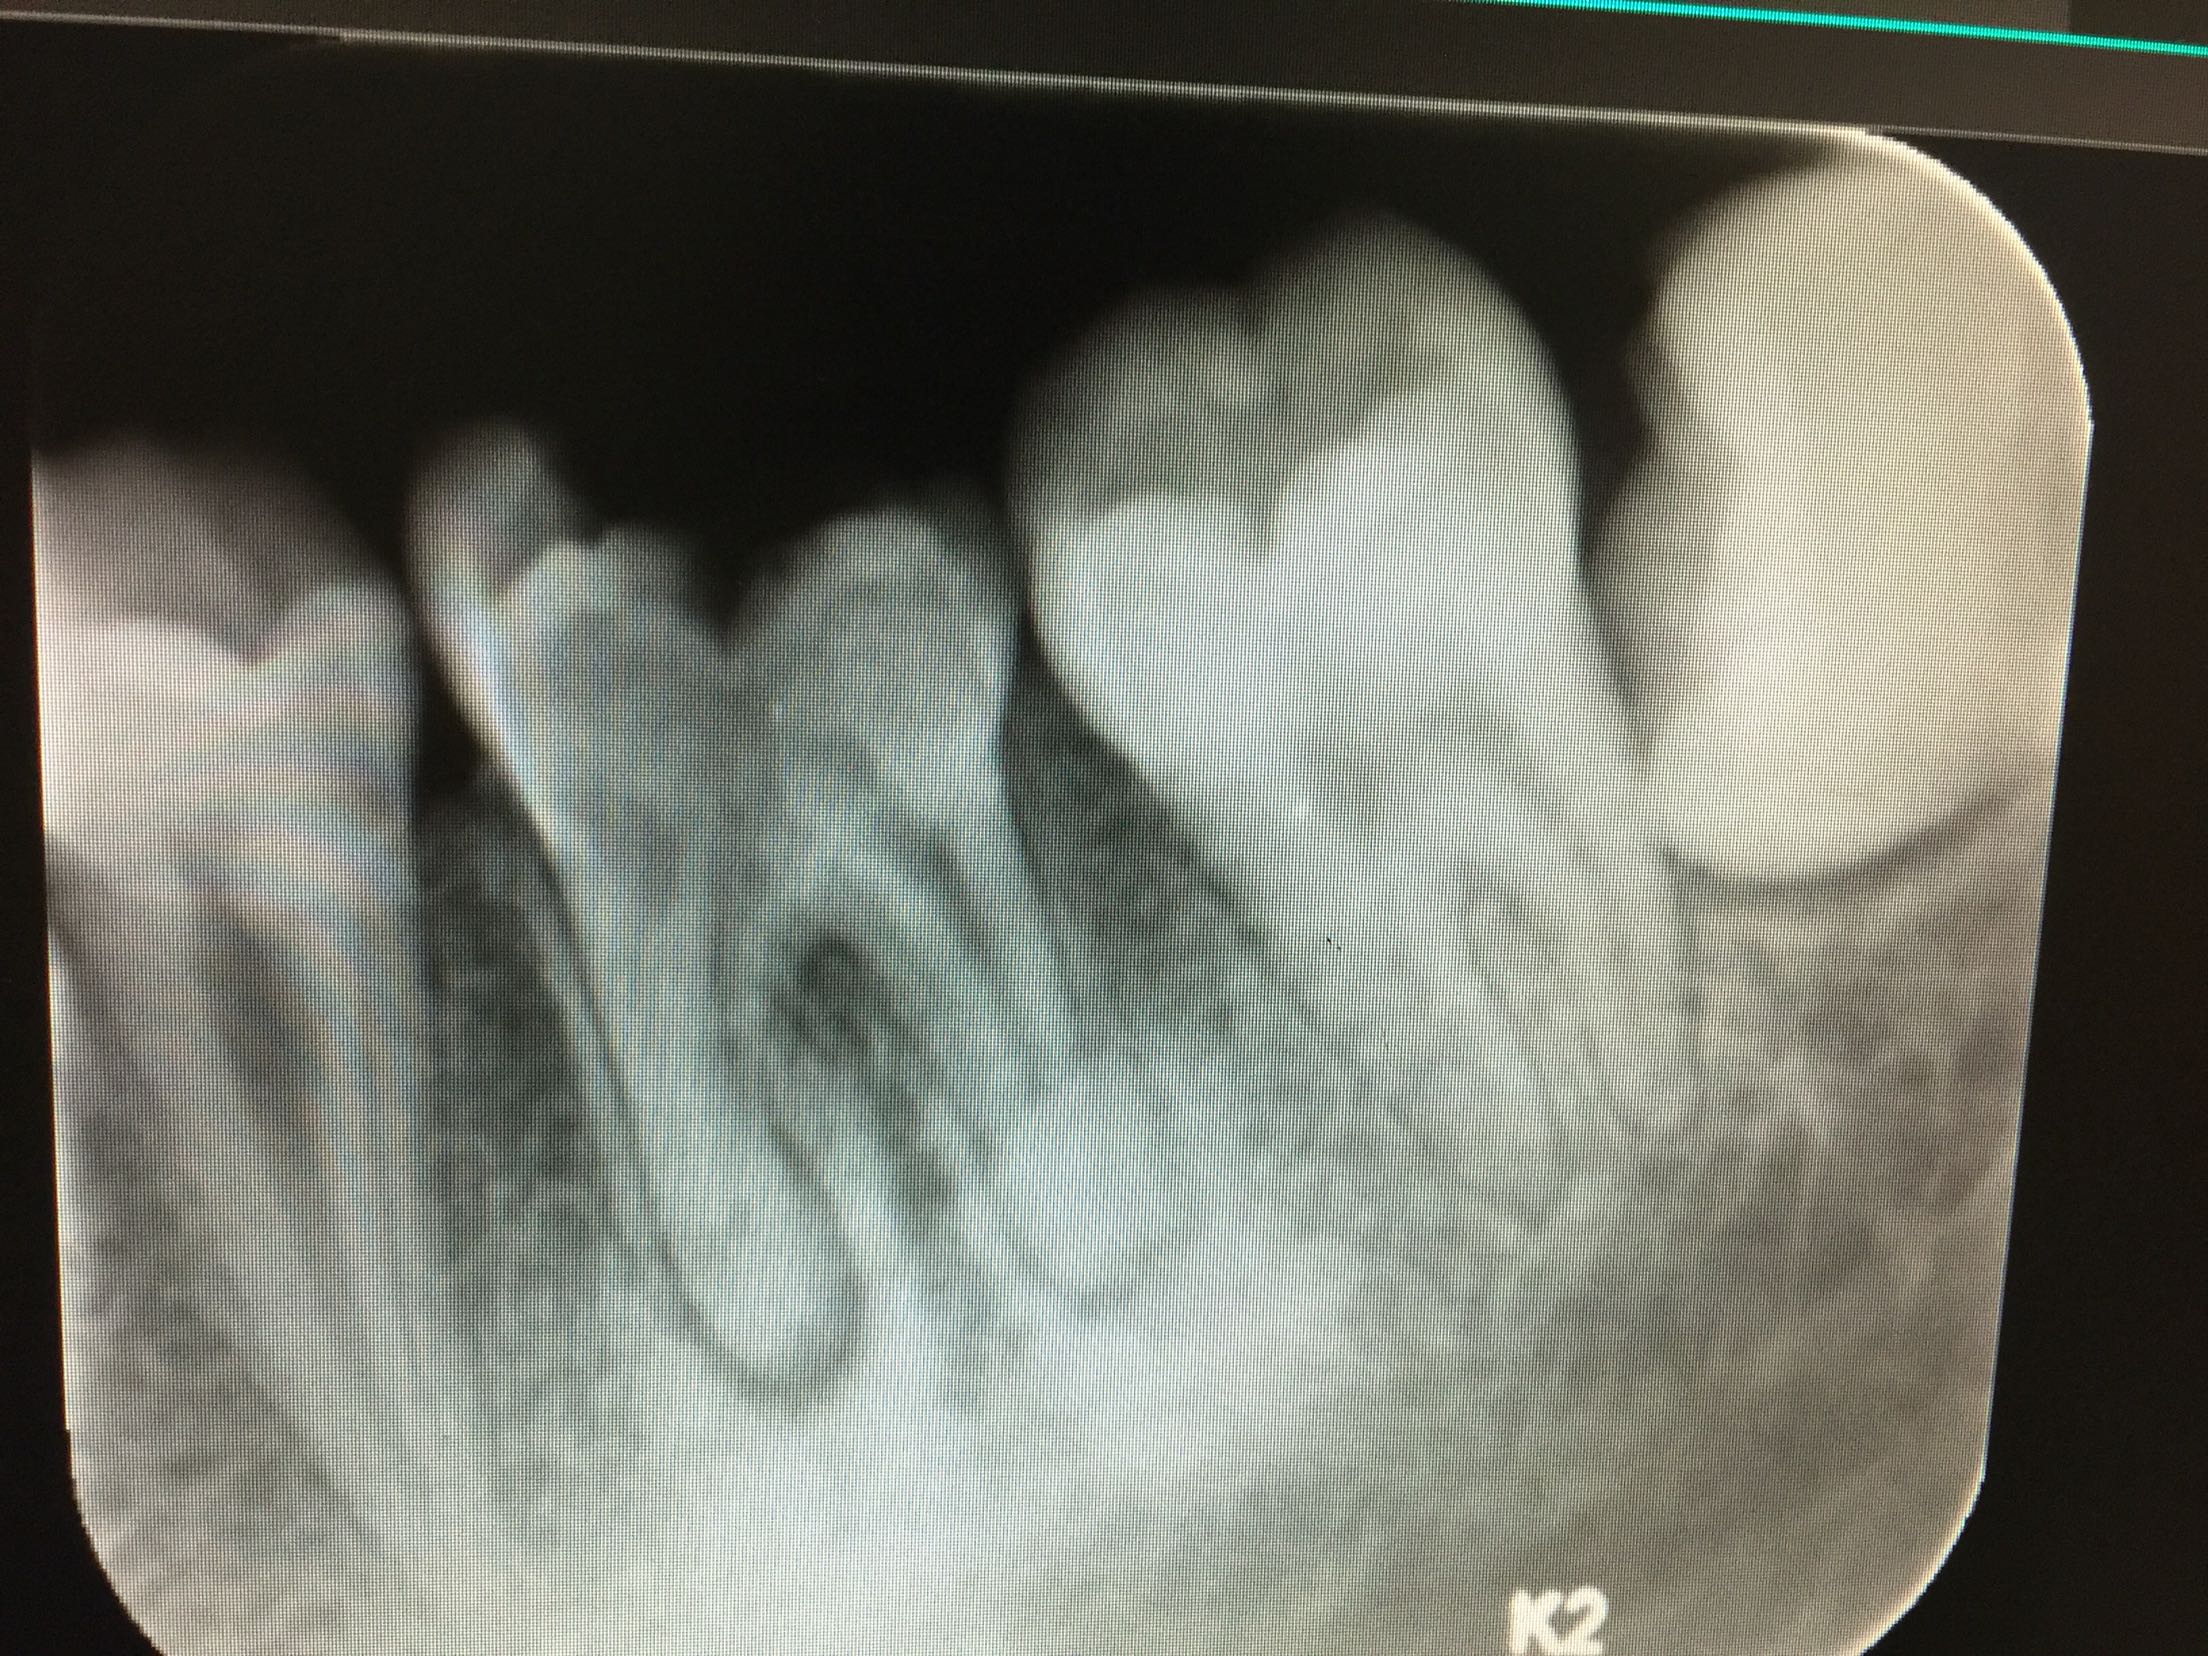

检查:全口卫生好,牙石+,软垢+,牙龈正常,无退缩。36牙远中邻合面龋,内有大量软龋,深达牙本质深层,已累及髓室底,冷-,探-,叩++,松+-。 X线:14牙颊合面可见龋坏,累及髓室底,未行根管治疗,根尖区有暗影。38牙近中阻生。

诊断:36根尖周炎 治疗计划:36牙拔除后行自体牙移植 治疗:拔除36牙后两周行自体牙移植(48牙),抗感染治疗,两周后复诊。